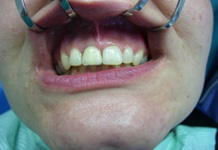

Klasickým příkladem a indikací pro použití implantátu je ztráta jednoho zubu (v tomto případě v předním – frontálním úseku) v jinak zdravém, nepoškozeném chrupu.

Nejčastější příčinou takové ztráty je sportovní nebo dopravní úraz.